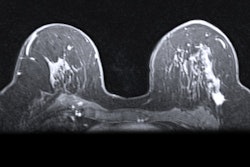

In this talk, researchers will demonstrate how initial ultrafast dynamic contrast-enhanced MRI (DCE-MRI) can aid in predicting complete pathologic response in breast cancer patients.Dr. Toulsie Ramtohul from the Paris Sciences et Lettres Research University will present the study, which looked at the links between perfusion parameters on initial ultrafast DCE-MRI and early prediction for pathological response after neoadjuvant chemotherapy in patients.

The researchers looked at six parameters in their prospective study of 50 women with an average age of 49 years. Out of these, 20 achieved pathologic complete response, while 25 had residual cancer burden.

Out of the six parameters explored, one showed promise in prediction. This parameter, known as the wash-in slope, measures the slope between the time of contrast inflow onset and the time of peak intensity in breast tumors.

The team found that a wash-in slope cutoff value of 1.6% per second had a sensitivity of 94% (17 of 18 women) and a specificity of 59% (19 of 32 women) for complete pathologic response. Wash-in slope also was also the factor most associated with predicting complete pathologic response.

Also, an area under the receiver operating characteristic curve (AUC) of 0.92 was achieved with a prediction model using the wash-in slope cutoff value, tumor-infiltrating lymphocytes, and HER2 positivity.